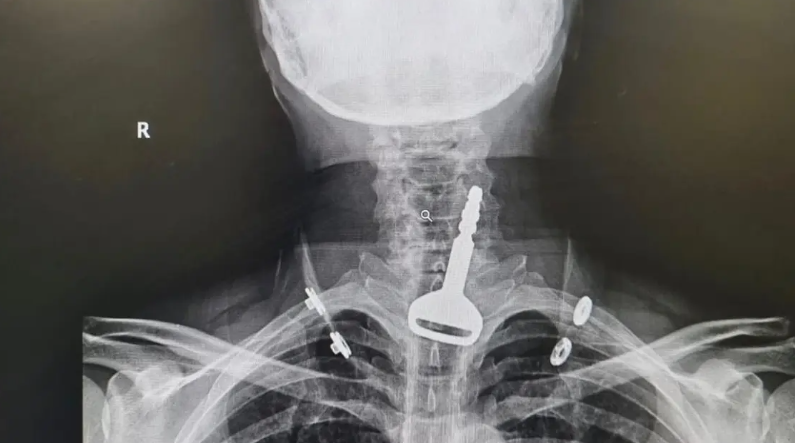

وأوضحت صحة مدينة القنفذة أن المريض، البالغ من العمر 49 عاماً، وصل لقسم الطوارئ وهو يعاني من انسداد بمجرى التنفس، ليتضح بعد الفحص السريري والأشعة وجود مفتاح سيارة عالق في القصبة الهوائية.

واعترف المريض للأطباء المعالجين بأنه ابتلع المفتاح أثناء لهوه به، ما تسبب له في حالة اختناق جزئي تطلب التدخل الجراحي عن طريق المنظار لاستخراج الجسم المعدني العالق.

وتقرر فورًا إدخال المريض قسم العمليات وتكثيف العناية الصحية له لكونه مريض قلب، وتم إجراء التدخل الجراحي عن طريق المنظار واستخراج المفتاح، ومن ثم متابعة الحالة عن طريق قسم التنويم لحين استقرار حالته الصحية وخروجه بالسلامة.